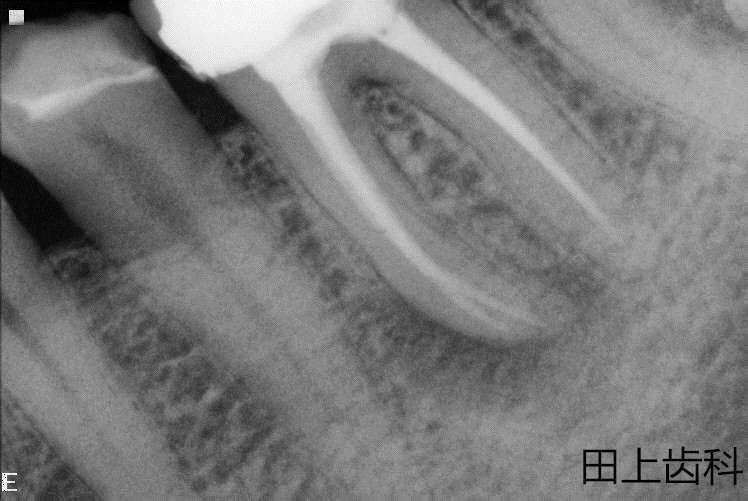

根管治疗